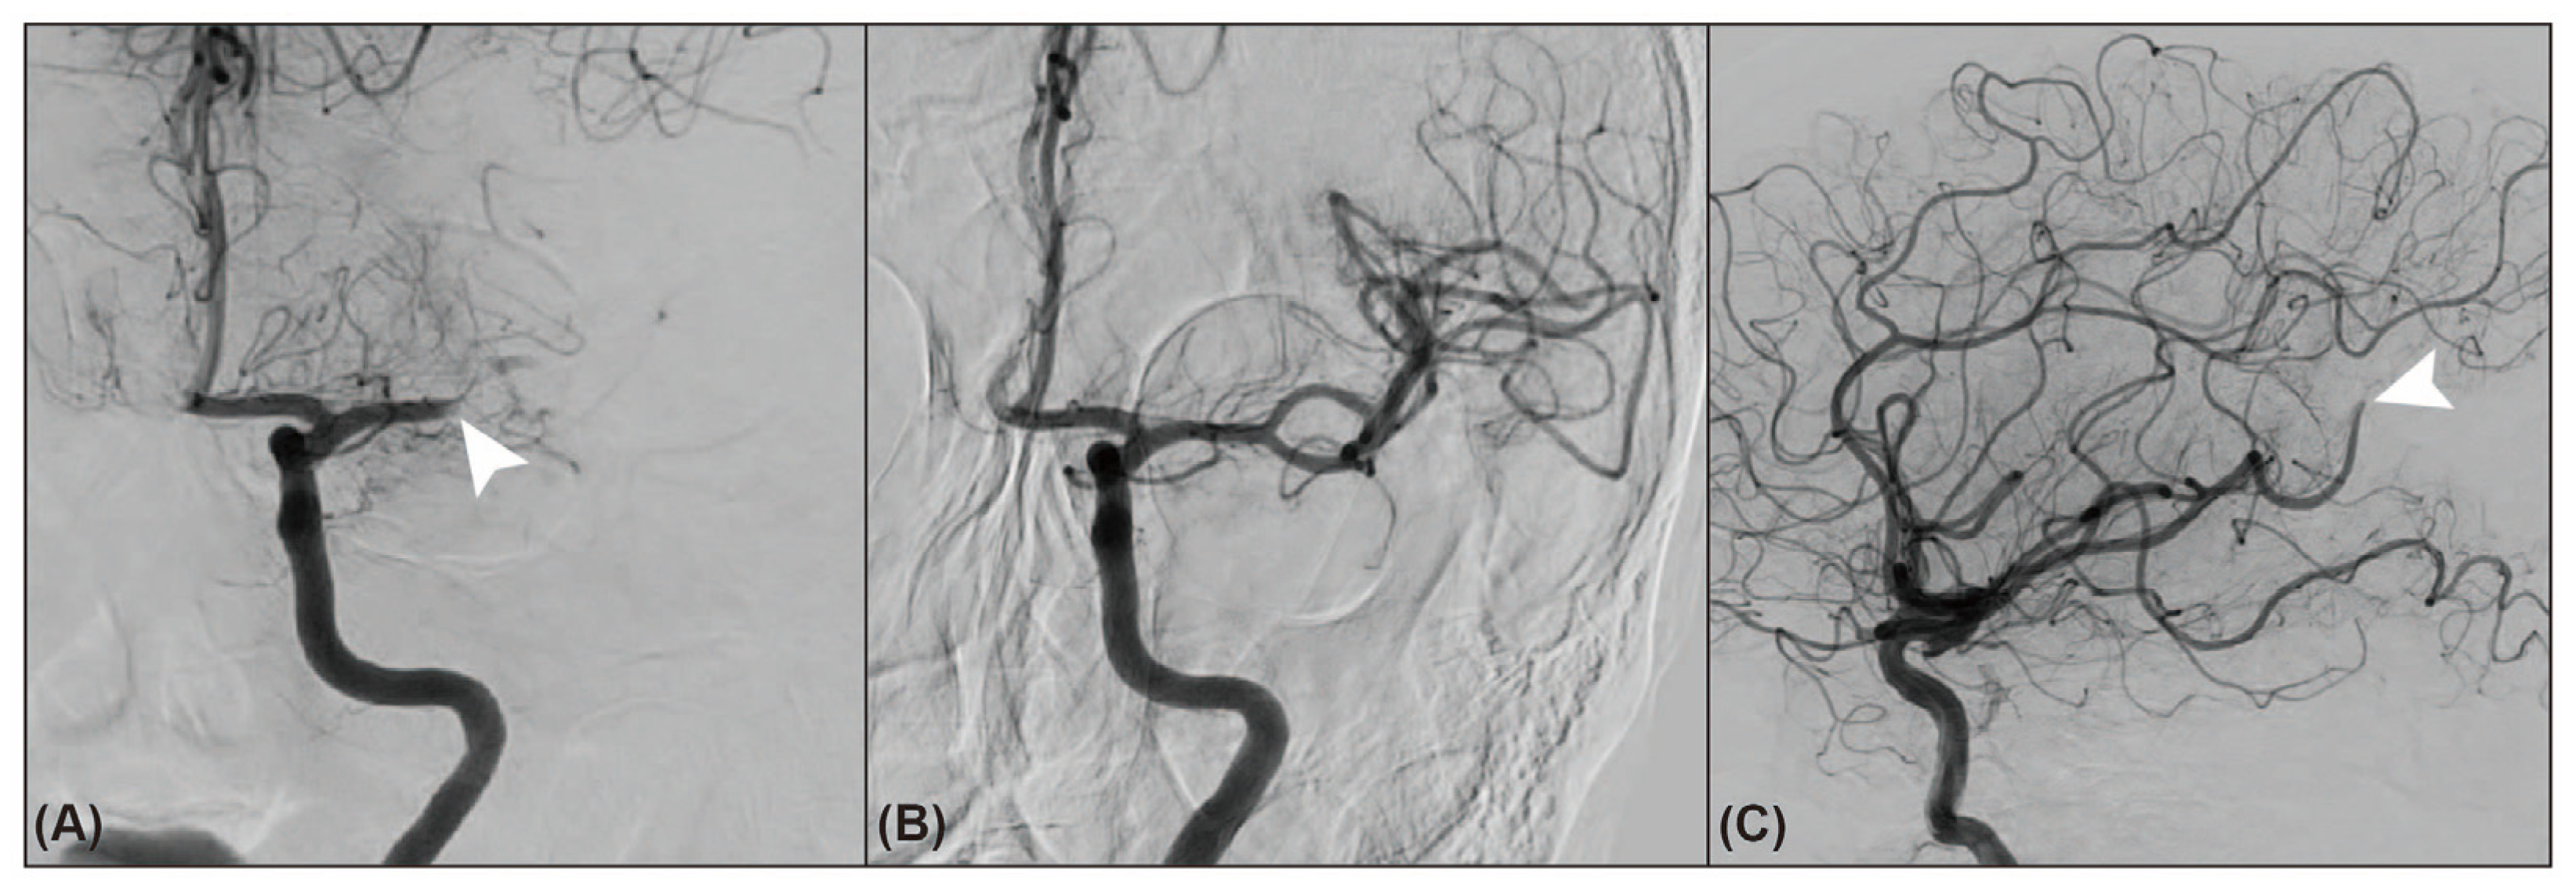

3.3. Endovascular Trajectory of Downstream Occlusion